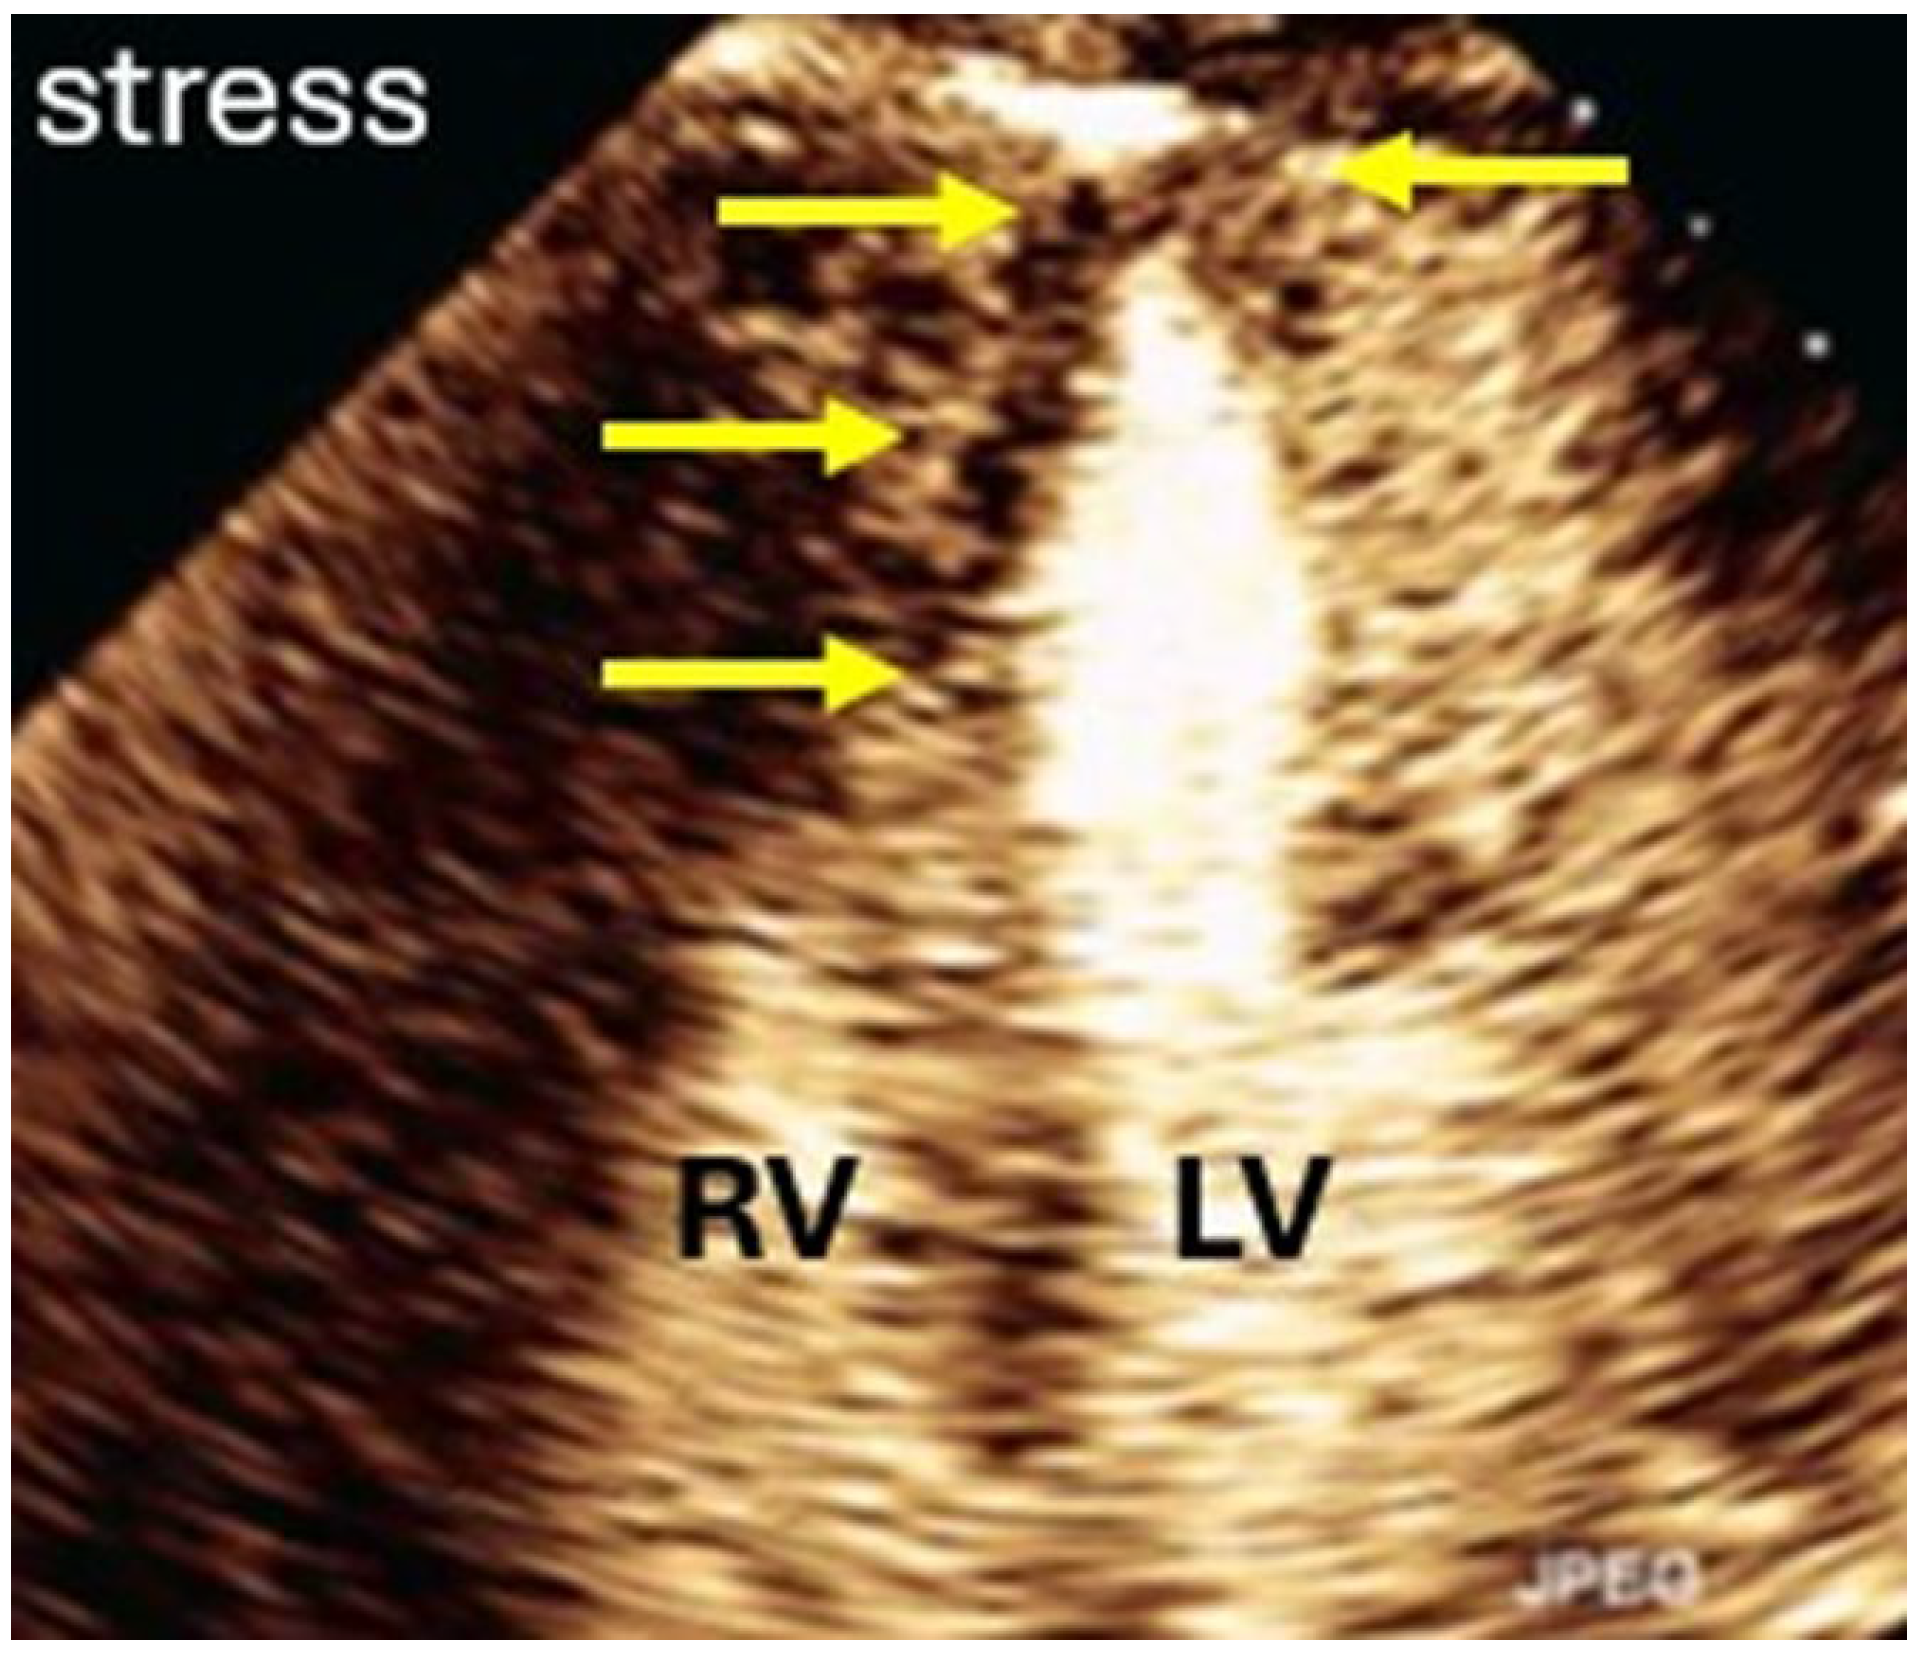

| Imaging method | Low-MI-contrast-specific imaging, additional intermediate-MI imaging in case of apical aneurysm for assessment of thrombus in the aneurysm |

| Imaging planes | Standard apical views and apical sweeps to assess the aneurysm for thrombi |

| Contrast application | Bolus injections |

| Typical finding | 1. Hourglass/ace-of-spades shape of apical LV cavity 2. Apical myocardium appears dark in late systole due to compression of the intramyocardial vessels 3. Apical aneurysms +/− thrombi in some patients |

| Alternative imaging | MRI useful for scar/fibrosis imaging and display of apical aneurysms CT in patients with contraindication for MRI and UEAs |